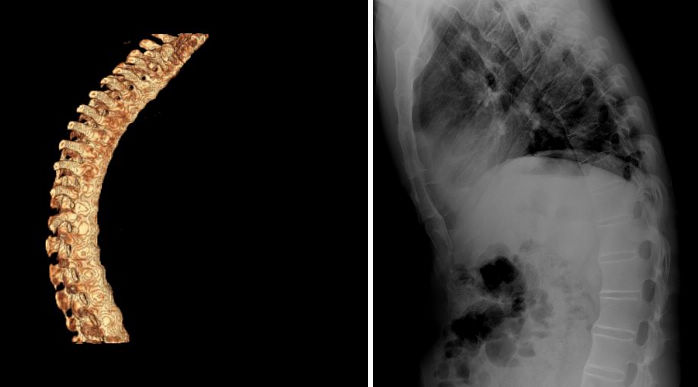

AS病人多有关节病变,且绝大多数首先侵犯骶髂关节,以后上行发展至颈椎。少数病人先由颈椎或几个脊柱段同时受侵犯,也可侵犯周围关节,早期病变处关节有炎性疼痛,伴有关节周围肌肉痉挛,有僵硬感,晨起明显;也可表现为夜间疼,经活动或服止痛剂缓解。随着病情发展,关节疼痛减轻,而各脊柱段及关节活动受限和畸形,晚期整个脊柱和下肢变成强硬的弓形,向前屈曲。

⑵腰椎病变:腰椎脊柱受累时,多数表现为下背前和腰部活动受限。腰部前屈、扣挻、侧弯和转动均可受限。体检可发现腰椎脊突压痛,腰椎旁肌肉痉挛;后期可有腰肌萎缩。

⑶胸椎病变:胸椎受累时,表现为背痛、前胸和侧胸痛,最常见为驼背畸形。如肋椎关节、胸骨柄体关节、胸锁关节[19、20]及肋软骨间关节受累时,则呈束带状胸痛,胸廓扩张受限,吸气咳嗽或打喷嚏时胸痛加重。严重者胸廓保持在呼所状态,胸廓扩张度较正常人降低50%以上,因此只能靠腹式呼吸辅助。由于胸腹腔容量缩小,造成心肺功能和消化功能障碍。

⑷颈椎病变:少数病人首先表现为颈椎炎,先有颈椎部疼痛,沿颈部向头部臂部放射。颈部肌肉开始时痉挛,以后萎缩,病变进展可发展至颈胸椎后凸畸形。头部活动明显受限,常固定于前屈位,不能上仰、侧弯或转动。严重者仅能看到自己足尖前方的小块地面,不能抬头平视。

脊柱病变的X线表现,早期为普遍性骨质疏松,椎小关节及椎体骨小梁模糊(脱钙),由于椎间盘纤维环附带部椎骨上角和下的破坏性侵蚀,椎体呈“方形椎”,腰椎的正常前弧度消失而变直,可引起一个或多个椎体压缩性骨折。病变发展至胸椎和颈椎椎间小关节,间盘间隙发生钙化,纤维环和前纵行韧带钙化、骨化、韧带骨赘形成,使相邻椎体连合,形成椎体间骨桥,呈最有特征的“竹节样脊柱”。